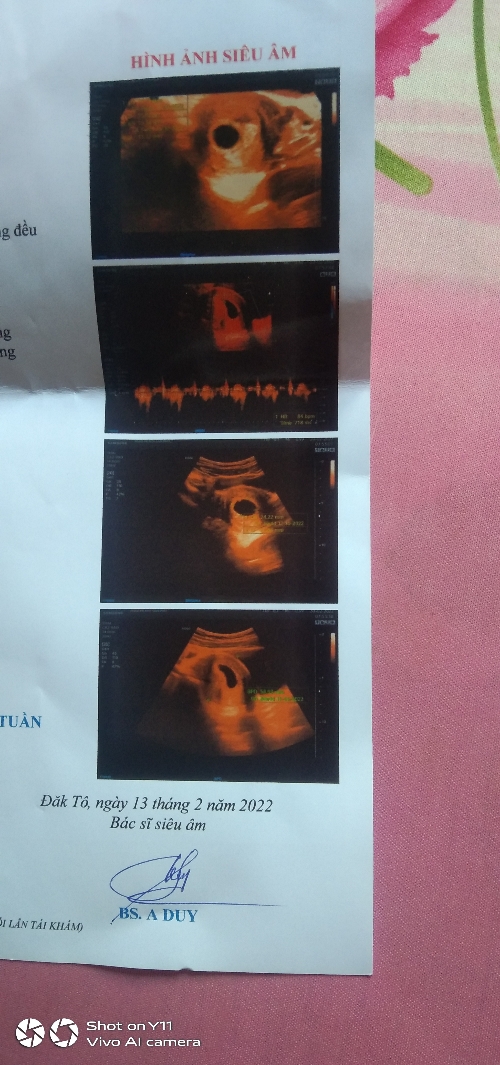

Chào bác sĩ ! Em đi khám thai tuần trước ngày 15 /2 thì thai được 5 tuần và chưa có tim thai , sang tuần nay hôm nay ngày 20/2 bác sĩ hẹn tái khám siêu âm thì đã có tim thai nhưng nhịp đập chỉ 90/ phút như vậy có sao không ạ? Bác sĩ còn đưa một mớ thuốc về uống em mới uống liều 1 thì thấy hơi chóng mặt mệt mỏi ạ